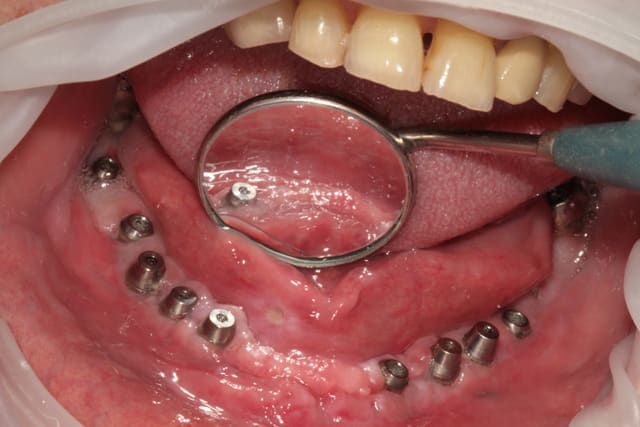

le contrôle de plaque va être très difficile pour ton patient avec les balcons de résine présents en vestibulaire des implants.

Je te poste une photo de ce genre de construction prothétique que je vois quotidiennement chez des patients qui me sont adressés pour des problèmes de peri-implantite.

Penser à la rigidité de ton bridge c'est bien mais il y a d'autres éléments qui sont tout aussi importants et qui ne faut pas négliger pour la pérénité de ta reconstruction implantaire.

Nobel ou autre, là n'est pas le problème. Il s'agit de la forme donnée à la suprastructure qui me gêne. C'est un élément capital pour permettre à nos patients d'accéder à la zone muqueuse periimplantaire et c'est un des rares élément que l'on peut influencer à 100%.

Il ne faut pas se leurer, l 'attache periimplantaire étant plus fragile que l'attache parodontale, un contrôle de plaque insuffisant s'accompagne très rapidement d'une inflammation periimplantaire avec les conséquences qu'on connaît. C'est sûr qu'un implant difficile à brosser est un implant difficile à sonder également! On ne peut diagnostiquer que ce que l'on voit.